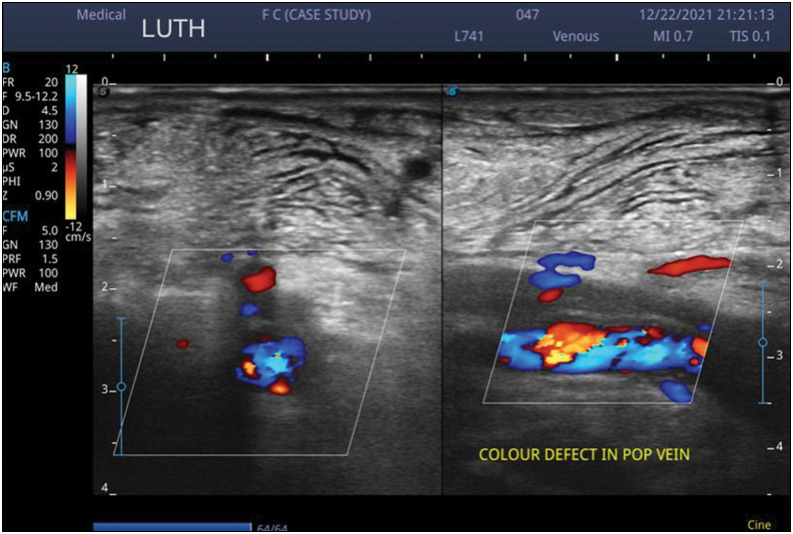

深静脉血栓形成(DVT)是世界范围内的突发公共卫生事件,也是造成全球疾病负担的主要因素。这是一个重要的原因发病率和死亡率在卧床病人,特别是那些与下肢骨折。早期发现深静脉血栓对患者的生存至关重要。本研究旨在评估住院骨科患者下肢深静脉血栓形成(LEDVT)的三重声像图特征,并确定与其发展相关的危险因素。这是一项描述性横断面研究,共有80名参与者:40名患有骨盆和下肢骨折(PELEF)的住院成人骨科患者和40名没有PELEF(非PELEF)的住院成人骨科创伤患者。在纳入研究前,获得机构伦理委员会的伦理批准,并得到所有参与者的同意。采用风险评估问卷对发生深静脉血栓的危险因素进行评估。对受试者进行威尔斯评分、d -二聚体测定和双下肢静脉三倍多普勒超声扫描。多普勒超声扫描发现7名(8.8%)参与者深静脉血栓形成。d -二聚体试验21例(52.5%)阳性,19例(47.5%)阴性。超声DVT结果与LEDVT患者的Wells评分相关。发生DVT的最高危险因素是近期卧床不起(92.5%)和重大创伤(87.5%),70.0%的LEDVT参与者和67.5%的非LEDVT参与者观察到这两个因素。与非PELEF对照组相比,PELEF组的LEDVT发生率更高。在本研究中,重大创伤、近期固定和侧浅静脉是深静脉血栓形成的主要危险因素。

Deep venous thrombosis (DVT) is a public health emergency worldwide and a major contributor to the global disease burden. It is a significant cause of morbidity and mortality amongst bedridden patients, especially those with lower extremity fractures. Early detection of DVT is crucial for the survival of the patient. This study aimed to assess the triplex sonographic features of lower extremity deep venous thrombosis (LEDVT) and identify risk factor(s) that are associated with its development in hospitalized orthopaedic patients. This was a descriptive cross-sectional study of a total of 80 participants: 40 hospitalized adult orthopaedic patients with pelvic and lower extremity fractures (PELEF) and 40 hospitalized adult orthopaedic trauma patients without PELEF (non-PELEF). Ethical approval was obtained from the institutional ethics committee and consented to by all the participants before inclusion. The risk factors for DVT were assessed using a risk assessment questionnaire. Wells score, D-dimer assay, and triplex Doppler ultrasound scanning of both lower limb veins were performed on the participants. Doppler ultrasound scan detected DVT in seven (8.8%) participants. D-dimer test was both positive in 21 (52.5%) and negative in 19 (47.5%) participants. Sonographic DVT findings correlated with Wells scores in those with LEDVT amongst cases. The highest occurring risk factors for DVT were being recently bedridden (92.5%) and major trauma (87.5%) which were observed in 70.0% of participants with LEDVT and 67.5% without LEDVT. LEDVT occurred more in the PELEF case group compared to the non-PELEF controls. Major trauma, recent immobilization, and collateral superficial veins were the major risk factors for DVT in this study.